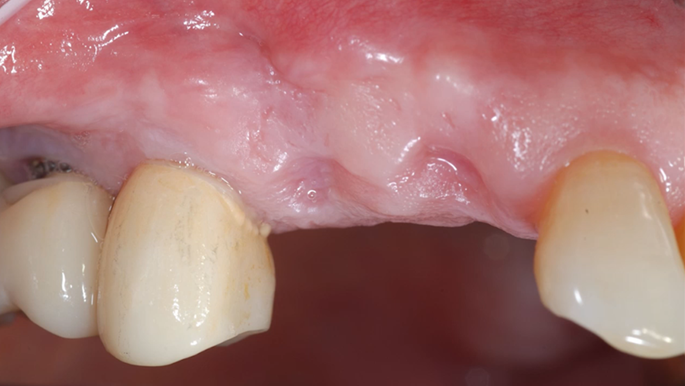

“Does guided surgery always mean flapless surgery? ”

Clinical case: R2GATE GUIDE surgery with GBR

- Courtesy of Dr. Kwang Bum Park, Korea -

Dr. Kwang Bum Park, digital guided surgery, bone regeneration, maxillary posterior, #13, #14, guided surgery, GBR, AnyRidge, i-GEN, Mega-Oss, R2GATE, R2GATE Full surgical kit

AnyRidge implant system, R2GATE Guide, R2GATE surgical kit (AnyRidge), Mega ISQ, Mega-Oss